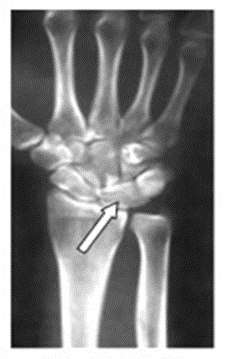

Na zamieszczonym obrazie radiologicznym nadgarstka strzałką wskazano kość

A. księżycowatą.

B. grochowatą.

C. łódeczkowatą.

D. haczykowatą.